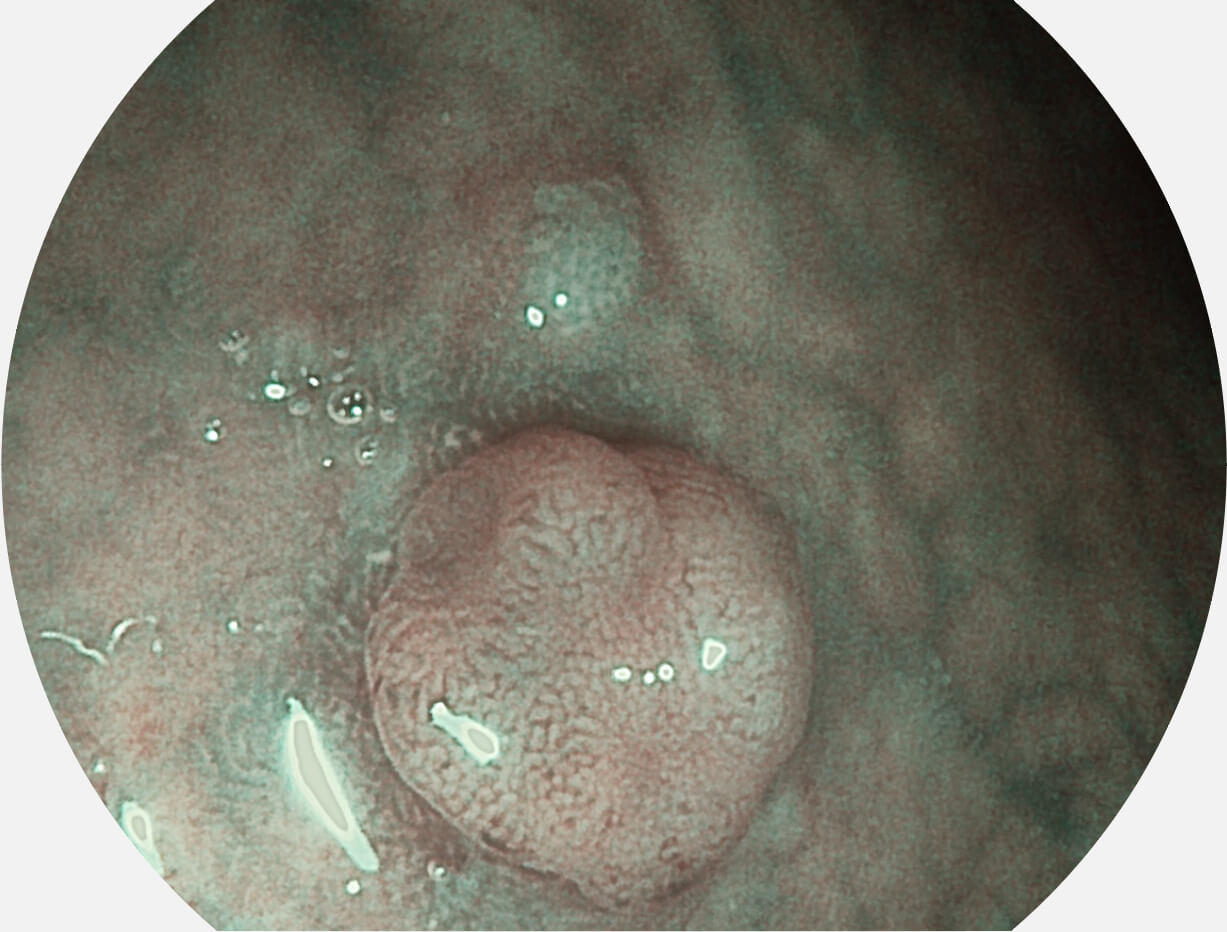

图像具有高亮度、高黏膜血管颜色对比度的特点,且不改变粘液、食物残渣、粪便的基本颜色,可在中远景下进行观察,助力消化道早期疾病的诊断。

SFI图像

白光图像